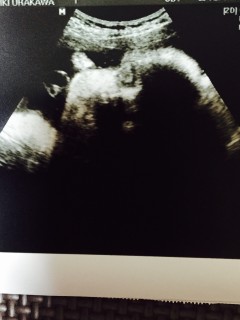

写真:35w2d:えりかさん:約2700g

今回は横顔を見せてくれました(^_^)鼻が高くて大きそうです(笑) 推定体重は2527gでBPDは9.18㎝、FLは6.73㎝の女の子です。 2週間前に比べて体重が2090g。2527gと500g近く増えていてびっくりしました

現在は37週で写真は35週の時